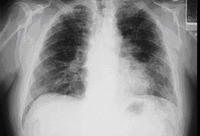

Chest x-ray of a patient with amiodarone pulmonary toxicity

From the collection of Athanasia Pataka, MD